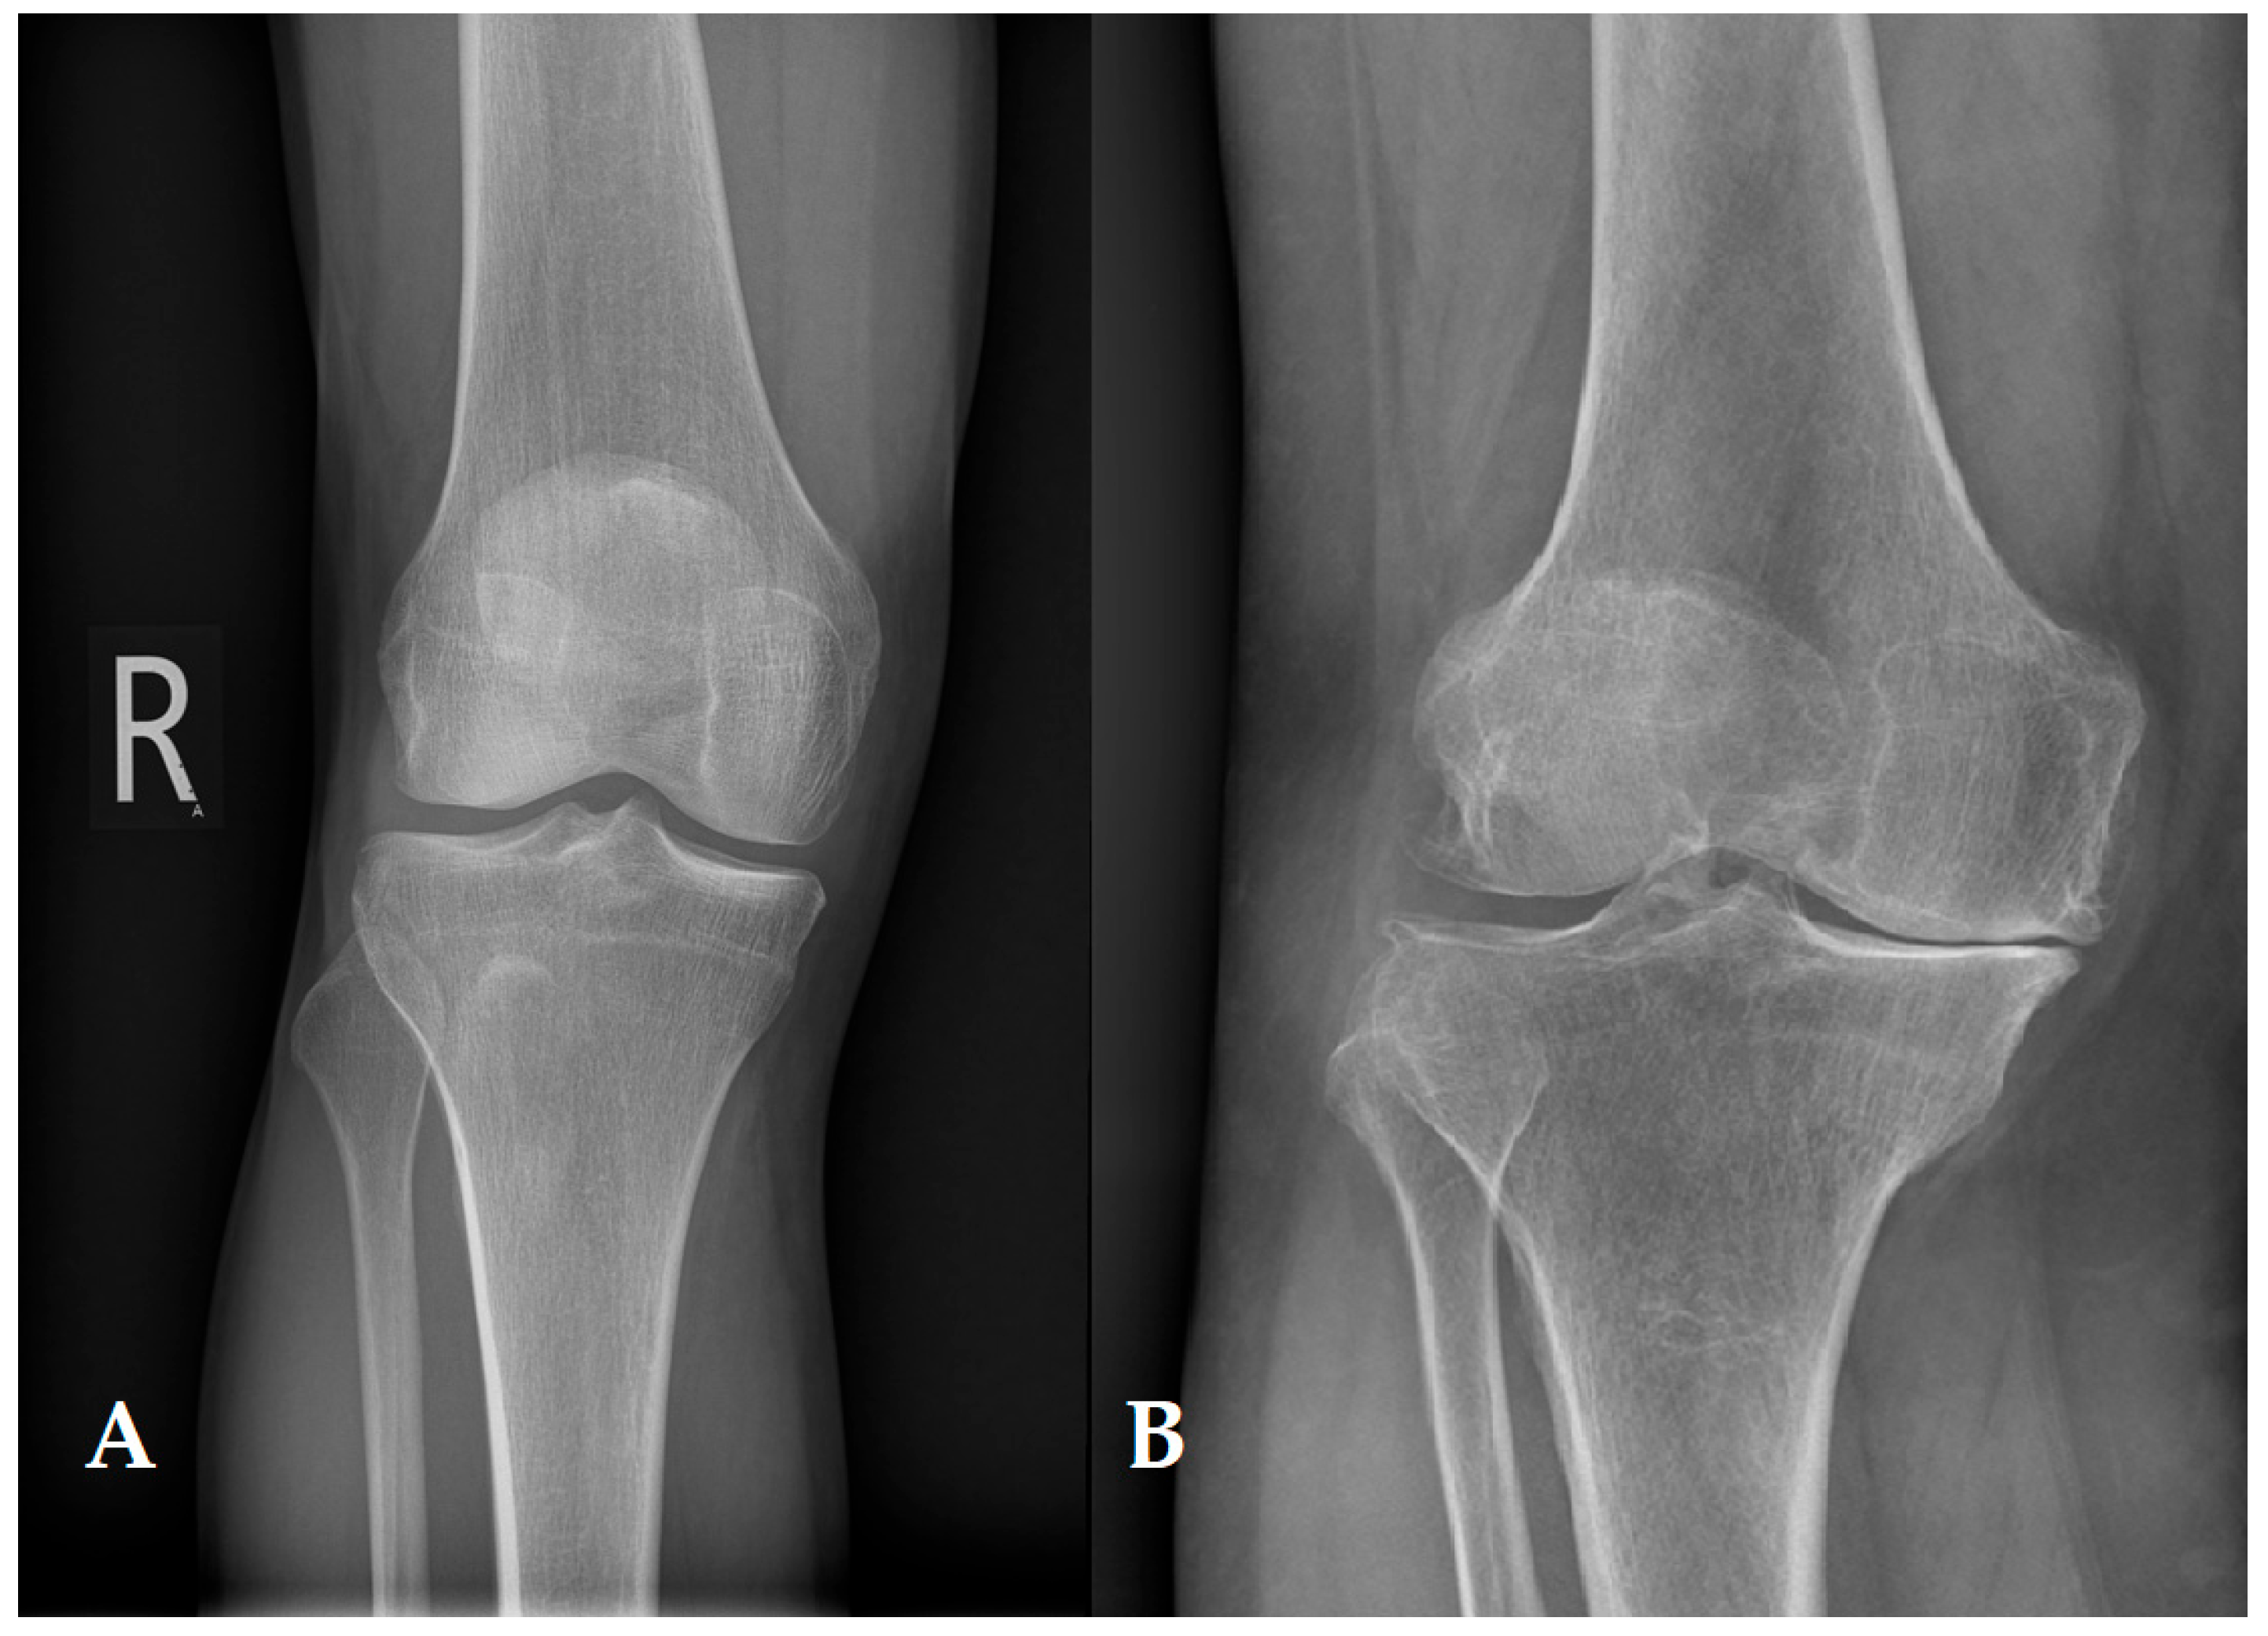

- Kellgren, J.H.; Lawrence, J.S. Radiological Assessment of Osteo-Arthrosis. Ann. Rheum. Dis. 1957, 16, 494–502. [Google Scholar] [CrossRef]

- Hayashi, D.; Roemer, F.W.; Guermazi, A. Imaging of Osteoarthritis by Conventional Radiography, MR Imaging, PET–Computed Tomography, and PET–MR Imaging. PET Clin. 2019, 14, 17–29. [Google Scholar] [CrossRef]